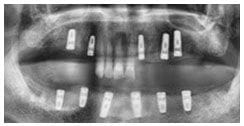

X 光片

術前X光片